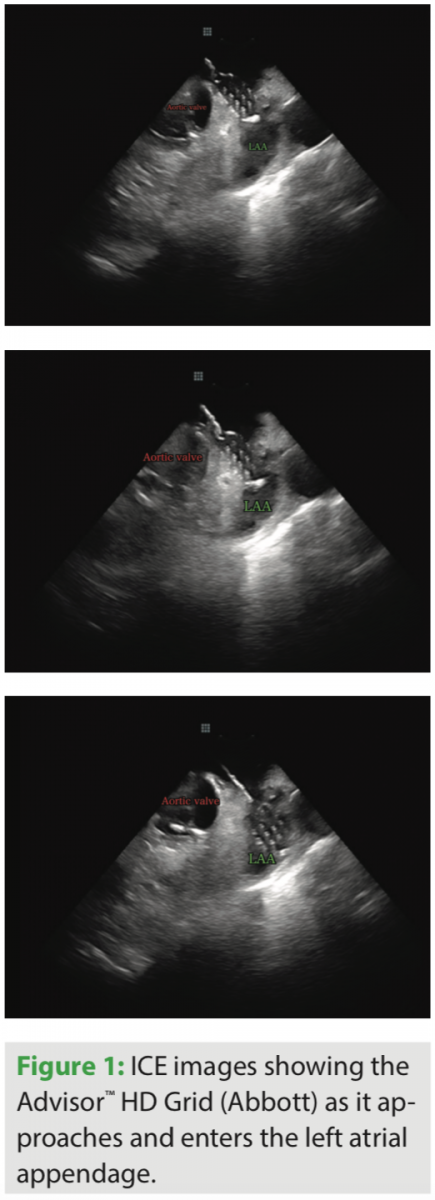

Beyond simply reducing fluoro exposure, I feel the use of ICE has significantly reduced my procedure time and complication rate, as well as improved my success rate. I use a number of non-standard views to optimize my ablation procedures. I routinely place the ICE catheter inside the left atrium for all left atrial procedures. If needed, for better visualization when addressing left ventricular tachyarrhythmias, I place the ICE catheter within the left ventricle. I frequently position the ICE catheter within the right ventricular outflow tract to address right ventricular outflow tract arrhythmias, and place the ICE catheter within the coronary sinus to improve visualization of the left atrium, left atrial appendage, and left ventricle.

I have been using the Advisor HD Grid for the past 6 months, and have been pleased with how this catheter has helped create detailed maps in a relatively short amount of time. I have found this catheter to be particularly useful for ablation of ventricular tachycardia and atrial tachycardia. I recently performed ablation of a PVC originating from the posteromedial papillary muscle and found that use of this catheter resulted in rapid acquisition of a very accurate activation map.